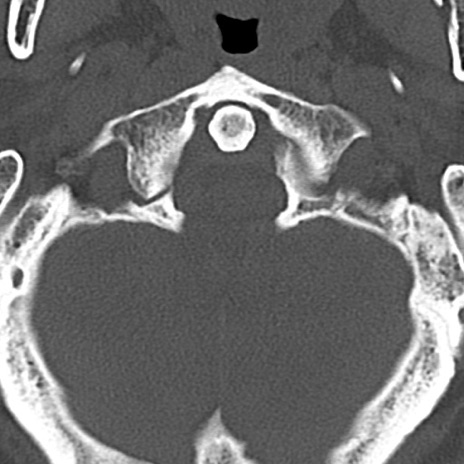

頚椎CT

横断像